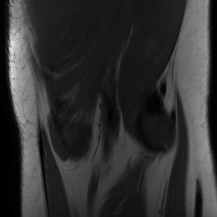

| Ground Truth | Initial | Global | LONDN-MRI | LONDN-MRI | Oracle |

| (1 iteration) | (2 iterations) | ||||

![]() |

| PSNR = dB | PSNR = 22.01 dB | PSNR = 29.02 dB | PSNR = 31.46 dB | PSNR = 31.74 dB | PSNR = 31.87 dB |